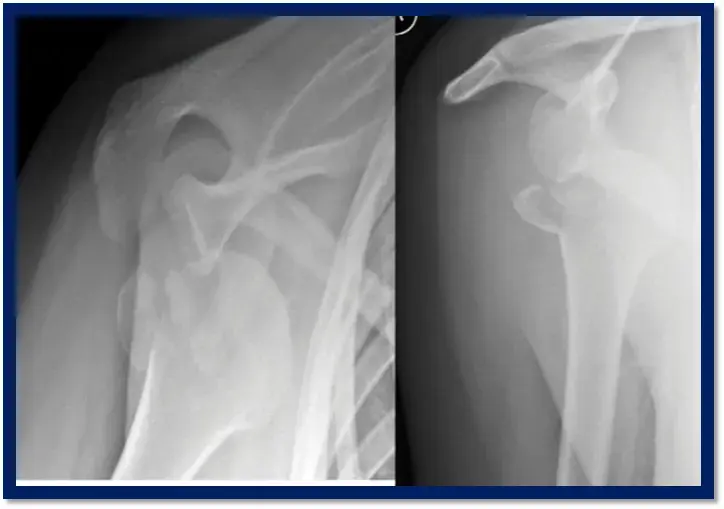

2. التصوير بالأشعة السينية (X-rays):

* الخطوة الأولى والأكثر شيوعًا، وتوفر صورًا أساسية لتحديد وجود الكسر وموقعه ونمط التبادل.

* عادة ما تُطلب صورًا متعددة (مثل الصور الأمامية الخلفية، والصور الإبطية، وصور "Y" scapular view) للحصول على رؤية ثلاثية الأبعاد للكسر.